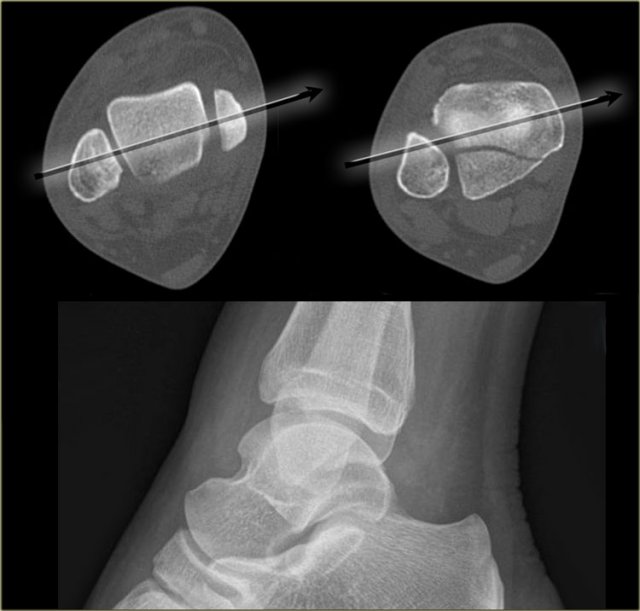

The distal fibula should project on the posterior part of the distal tibia The distal fibula should project on the posterior part of the distal tibia

Lateral view

Many think that for a good lateral view the distal fibula should be in the center of the distal tibia.

However, since the fibula is positioned more dorsally, the fibula should project over the posterior part of the distal tibia (arrow).

Malpositioning of the lateral view Malpositioning of the lateral view

Malpositioning of the Lateral view

Malpositioning of the lateral view is the most common mistake in radiography of the injured ankle.

Because the patient is in pain, the technologist is afraid to let the patient turn the ankle fully lateral.

This is one of the reasons why we miss so many fractures of the posterior malleolus.

The CT demonstrates a large tertius fracture.

On the lateral view and also on the AP- and Mortise views, which will be shown in the paragraph on tertius fractures, this fracture was not visible.

The explanation is that on the lateral radiograph the fibula projects in the middle of the tibia.

The x-ray beam is not parallel to the fracture line.

Since the fracture line of a tertius fracture always has this orientation, we must insist on a true lateral view.

Good positioning of the lateral view - Tertius fracture Good positioning of the lateral view - Tertius fracture

On a well positioned lateral view the tertius fracture is obvious (red arrow).

This was the only fracture that was seen on the x-rays of the ankle and this patient turned out to have an unstable Weber-C fracture and went for surgery.

The x-ray beam has to be centered on the malleoli.

Notice the exorotation of the foot for a proper lateral view.